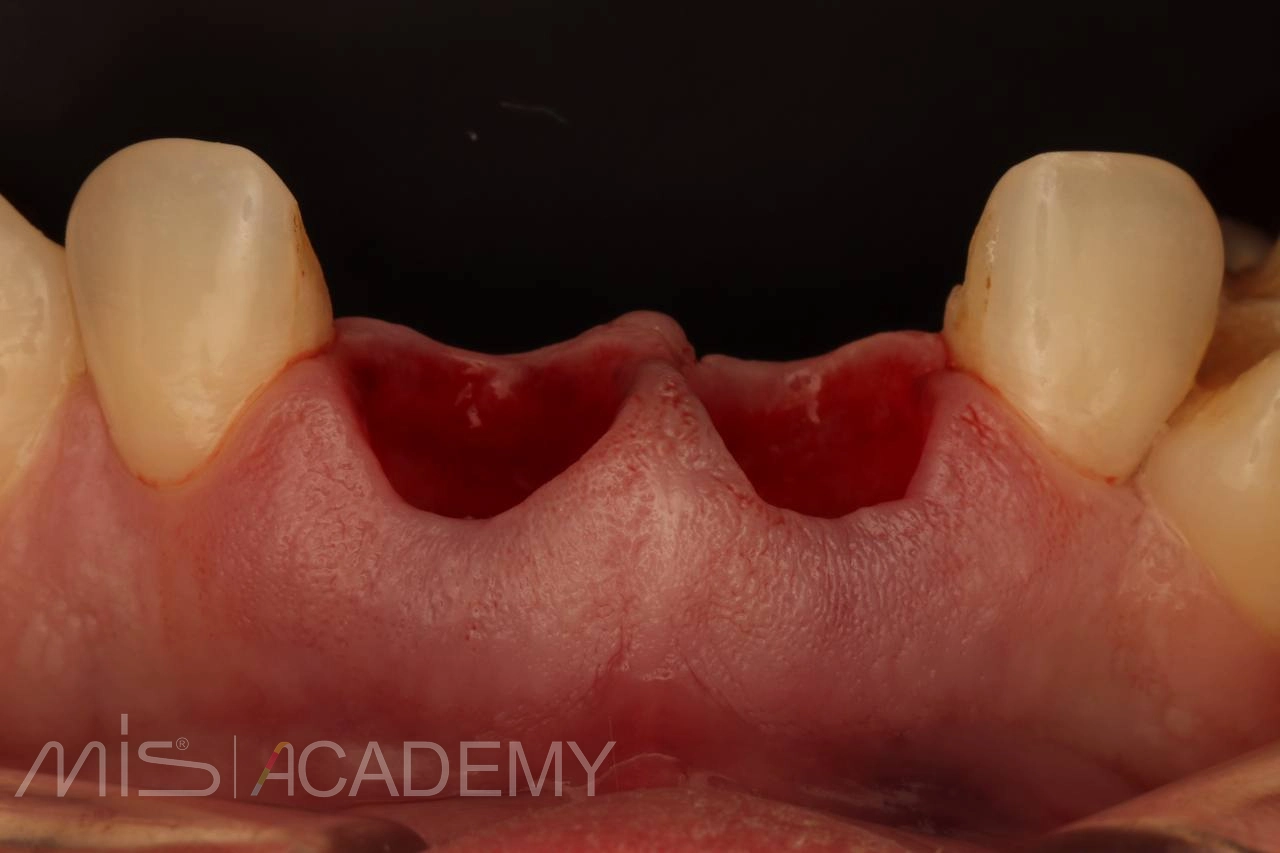

Сохранение объёма и архитектуры мягких тканей — основа успешной реабилитации фронтального отдела.

P.S. Обратите внимание на состояние мягких тканей. И да… смотрите под ноги 😉